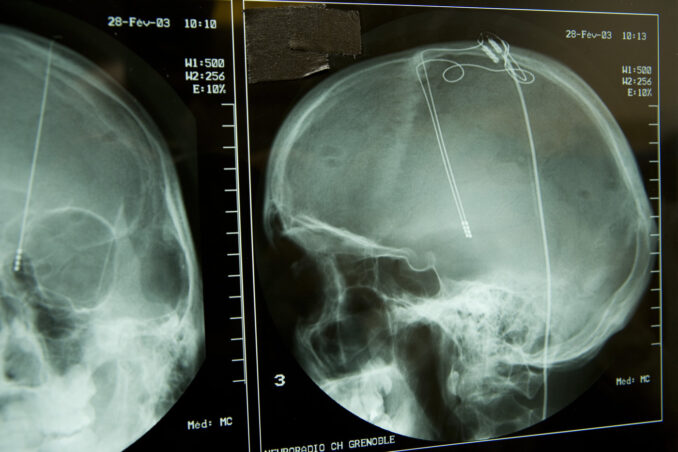

More than six million people worldwide suffer from Parkinson’s Disease. It is a disease that is often treated with what is known as “deep brain stimulation,” whereby a patient has centimeter-long electrodes implanted into their brain that stimulate certain areas.

It is a technique that is improving all the time, but it also has disadvantages. One of those disadvantages is that it involves fairly major surgery. A second disadvantage is that a patient has to undergo surgery not just one time but several times. This is because the electrical stimulator is connected to a battery that must be replaced every 3 to 5 years.